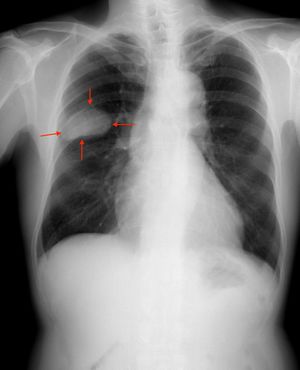

عادة ما يظهر سرطان الخلايا الصغيرة في الرئة في الشُعب الهوائية المركزية ويغزو الطبقة ما تحت المخاطية مما يؤدي إلى تضييق الممرات الهوائية. تشمل الأعراض الشائعة: السعال وضيق التنفس وفقدان الوزن والوهن. أكثر من 70٪ من المرضى الذين يعانون من سرطان الخلايا الصغيرة يتعرضون لمرض انبثاثي. يحدث الانبثاث في مواقع شائعة مثل: الكبد والغدة الكظرية والعظام والدماغ.

ينتشر سرطان الخلايا الصغيرة في أغلب الأحيان بسرعة أكبر وعلى نطاق أوسع من سرطان الرئة ذو الخلايا غير الصغيرة [8](وبالتالي تم تنظيمه بشكل مختلف). هناك عادة إصابة مبكرة في العقد اللمفاوية القمية و المنصفية.[7]